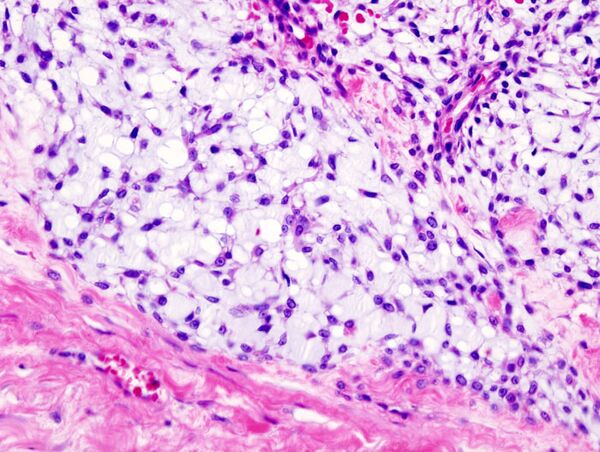

Гистограмма хондромы стенки грудной клетки. Окрашено гематоксилином и эозином.

Хондросаркома — злокачественная опухоль хрящевого строения. Хондросаркома периферической локализации хорошо выявляется в виде плотной опухоли, прилегающей к кортикальному слою кости, иногда прорастающей в кость на различную глубину. В ней могут быть очаги оссификации и петрификаты. Опухоль плотноэластической консистенции, при наличии ослизнения, распада или кровоизлияний — более мягкая, не имеет ясного ограничения от соседней ткани. При разрезе нетрудно определить хрящевой её характер. При микроскопическом исследовании опухоль напоминает иногда хондрому, состоит из незрелых клеток с резко выраженным клеточным атипизмом. Часто рисунок опухоли имеет вид микросаркомы, в которой можно найти участки хрящевой ткани с плохо оформленными ячейками, содержащие неправильной формы хондробласты.